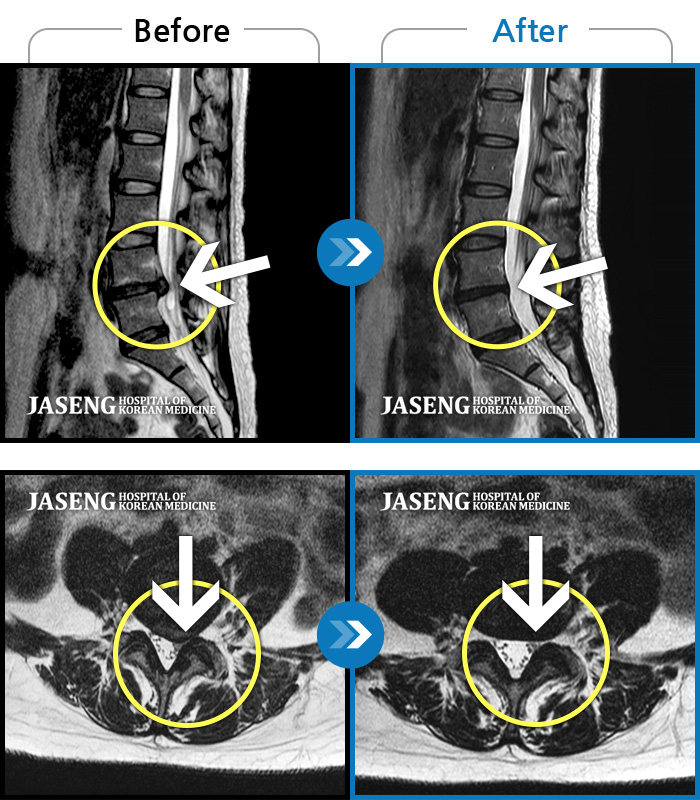

MRI 치료사례

허리, 다리의 극심한 통증으로 거동이 힘들고 일상생활과 정상적인 업무가 불가능한 상태에서 내원하신 환자분입니다.